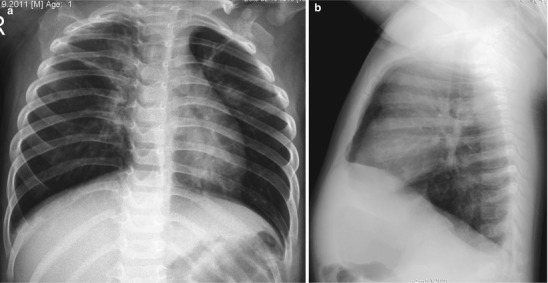

Typical chest radiographic appearances are peribronchial thickening/opacities, hyperaeration, and subsegmental atelectasis (Fig. 13.1). The peribronchial inflammation and edema manifests as increased peribronchial cuffing or thickening of the bronchial walls, which is usually asymmetric and radiates from the hila into the lung. Narrowed distal airway lumen due to bronchiolar wall edema and mucus results in hyperinflation with areas of segmental and subsegmental atelectasis (Condon 1991; Donnelly 2001). Patchy areas of airspace consolidation have also been described in viral pneumonia. CT is rarely required in the investigation of viral lower respiratory infection, but the most common CT feature is peribronchial thickening and ground-glass attenuation without consolidation (Tanaka et al. 1996).

Fig. 13.1.

Respiratory syncytial virus (RSV) infection in an 18-month-old boy. Frontal (a) radiograph demonstrates hyperaeration, perihilar peribronchial thickening, and areas of subsegmental atelectasis. Lateral view (b) shows depression of the diaphragm compatible with hyperaeration